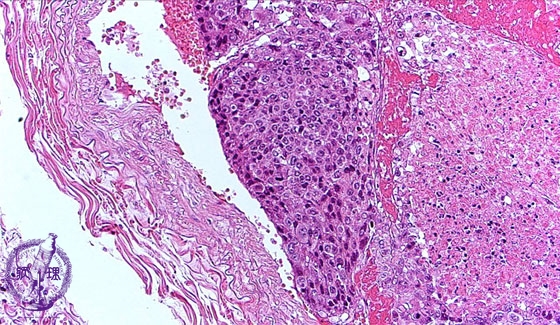

- 5.Lung, Pleura

- (20)Metastatic lung tumor

Microscopic view (HE stain, medium power view): Tumor embolus consists of poorly differentiated hepatocellular carcinoma with coagulative necrosis. On the right side of the tumor, necrosis is seen. In other areas, well differentiated hepatocellular carcinoma is seen.

Click the image to see the enlarged image.